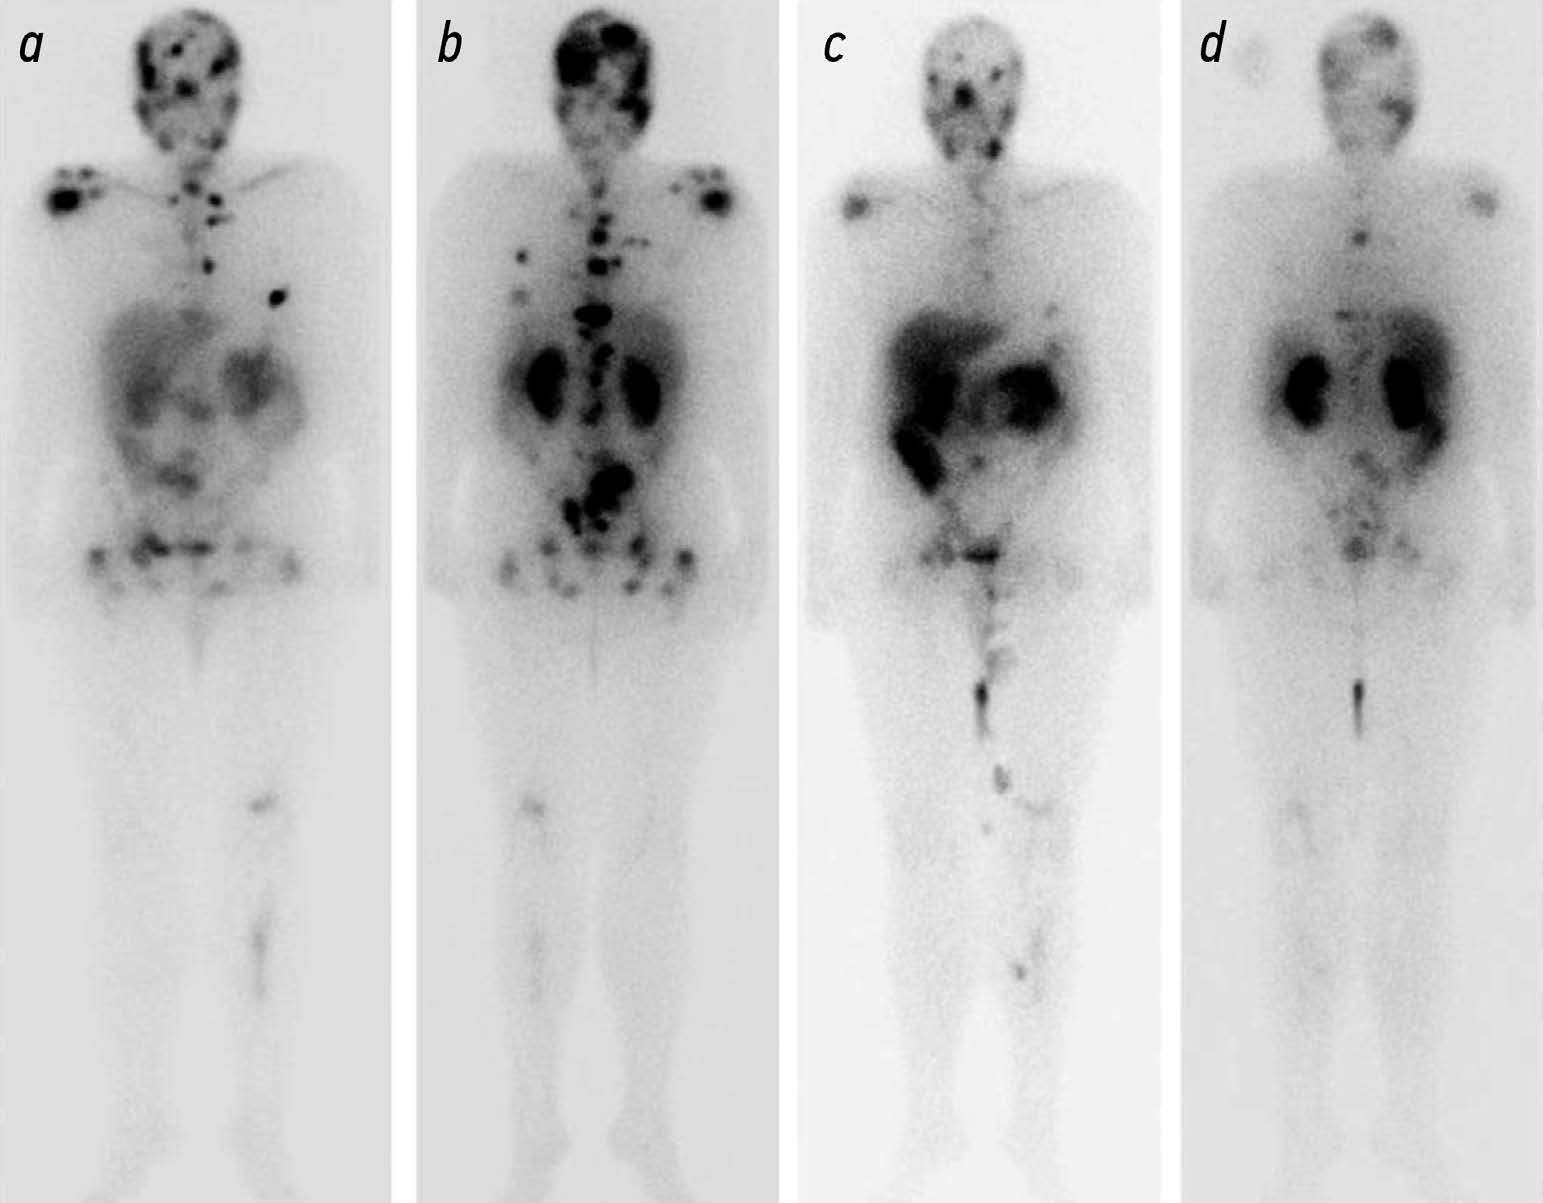

Potential use of radiation methods for diagnosing bone metastases of castration-resistant prostate cancer: a literature review

Abstract

Metastatic castration resistant prostate cancer (mCRPC) is the tumor progression with the development of resistance to androgen deprivation therapy. The incidence of bone metastases in these patients reaches 90%. Radiology is widely used to diagnose mCRPC. Computed tomography (CT) and magnetic resonance imaging (MRI) are beneficial in anatomic imaging, but have some limitations in evaluating effectiveness of disease treatment. Scintigraphy is used to screen for bone metastases, but is poorly suited for assessing disease progression. Positron emission tomography (PET) combined with CT and single photon emission CT are used for early detection of local or systemic spread of prostate cancer. PET of prostate specific membrane antigen is used to predict the effectiveness of anti tumor therapy based on the absorbed dose of a radiopharmaceutical (RP). The introduction of RPs (177Lu-PSMA) opens up new perspectives for radionuclide therapy with simultaneous evaluation of its efficacy using hybrid visualization. The potential use of radiology in the diagnosis of bone metastases is of particular interest for the analysis and systematization of the data obtained and for the development of indications for radioligand therapy and the evaluation of its efficacy.

Published data indicate that radiologic modalities for the diagnosis of mCRPC vary in sensitivity and specificity and have their own advantages and limitations, so these modalities should be combined.

The development and improvement of methods to quantitatively assess treatment efficacy and identify prognostic markers will enable more informed selection of treatment strategies and radiopharmaceuticals, leading to improved overall survival.

854-869